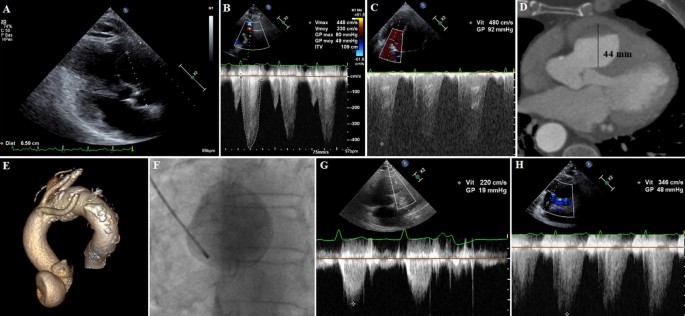

Transthoracic echocardiogram in parasternal shortaxis view shows an aneurysm of left sinus of Valsalva, a mildly dilated noncoronary sinus and a normal right sinus of Valsalva Figure 5) Transesophageal echocardiogram confirms aortic root dilation with an unruptured left sinus of Valsalva aneurysmThe sinuses of Valsalva are dilated cavities between the aortic leaflets and the ascending aortic wall They are subdivided into the left, right and posterior sinuses The sinuses are characterized structurally by their bulging shape protruding into the aortic wall They act as a buffer between the leaflets, giving rise to the left and rightMFS patients with highly dilated (the diameters were equal to or more than 39 mm) SoV (high group, n = 18) and MFS patients